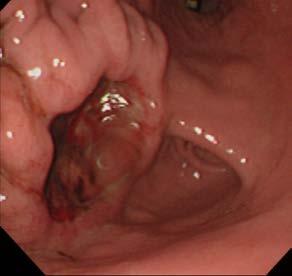

The skin and subcutaneous tissues were erythematous and extensively thickened over the ventral abdomen bilaterally, extending down both hindlimbs to the stifle region and cranially to caudal thorax. The thickening consisted of coalescing nodules with areas of ulceration and draining sinus tracts, as shown in the image of the ventral skin ( Figure 1).

Fine needle aspirates (FNA) were obtained from two subcutaneous nodules and impression smears from the ulcerated surfaces and stained with rapid Romanowsky stain (Rapid Diff, Australian Biostain). Image of the cytology smear is shown in Figure 2.

The smears are moderately cellular containing inflammatory cells and abundant round yeast organisms with occasional clusters of paired cocci bacteria in a light blue stippled proteinaceous background. The

Figure 1. Image of ventral abdominal skin lesions Figure 2. FNA from subcutaneous nodule (500x magnification)inflammatory cells are a mix of degenerate neutrophils, small lymphocytes and macrophages. Macrophages frequently contain yeasts and occasional neutrophils contain bacteria. The yeast are 5-15µm diameter with a thin pink cell wall and prominent unstained capsule (1-2µm diameter) and show rare narrow based budding.

Fungal and bacterial neutrophilic and histiocytic panniculitis/pansteatitis. Fungal morphology consistent with Cryptococcus species.

The clinical findings and cytology support cutaneous Cryptococcosis with secondary bacterial infection.

The cat was treated with Itraconazole 50mg SID and topically with Otoflush (Dermcare-Vet) and silver sulfadiazine ointment (Flamazine, Smith and Nephew). At recheck two weeks later, she had shown a 20% improvement with the skin remaining erythematous with some reduction in ulceration and minimal change in the subcutaneous nodules. She was changed to Fluconazole 50mg BID. At recheck another four weeks later, she had shown marked improvement as evident

in the image below (Figure 3). There were still multiple palpable nodular lesions in the subcutis but these had significantly reduced in size since the last visit (estimated 70% reduction) and there was one 8mm ulcer. Numerous Cryptococcus organisms were evident on FNA of a nodule and on a scraping of the ulcer. A liver profile biochemistry panel was normal with albumin 28.4g/L (RI 27-40). She was continued on Fluconazole 50mg BID with a plan to recheck in 8 weeks.